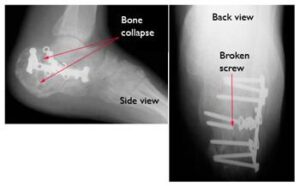

Risks of Premature Weight-Bearing

Placing weight on the foot too soon can disrupt the healing process:

- Bone fragments may shift, potentially requiring additional surgery.

- If surgery has been performed, screws may loosen or break, and the bone could collapse.

- While the initial weight-bearing attempt may seem uneventful, continued pressure on an unhealed bone can lead to hardware failure and delayed recovery.

Six months after surgery, this patient’s hardware has failed. Several screws have broken and the calcaneus has collapsed. This patient required major reconstruction, and today walks with a limp and has little motion in the foot.